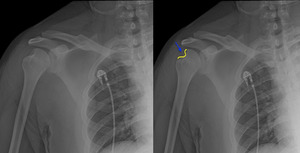

A 25-year-old man with a history of seizure disorder presented to the emergency department with right shoulder pain following a seizure. The patient had previously dislocated the same shoulder which he had reduced on his own. Radiographs revealed an anterior shoulder dislocation (Figure 1), with no fracture identified.

The shoulder was easily reduced on 1st attempt using 0.5mg/kg intravenous ketamine sedation. Post reduction radiographs confirmed the reduction, but also revealed a large Hill Sachs deformity (Figure 2), likely the result of recurrent dislocations.